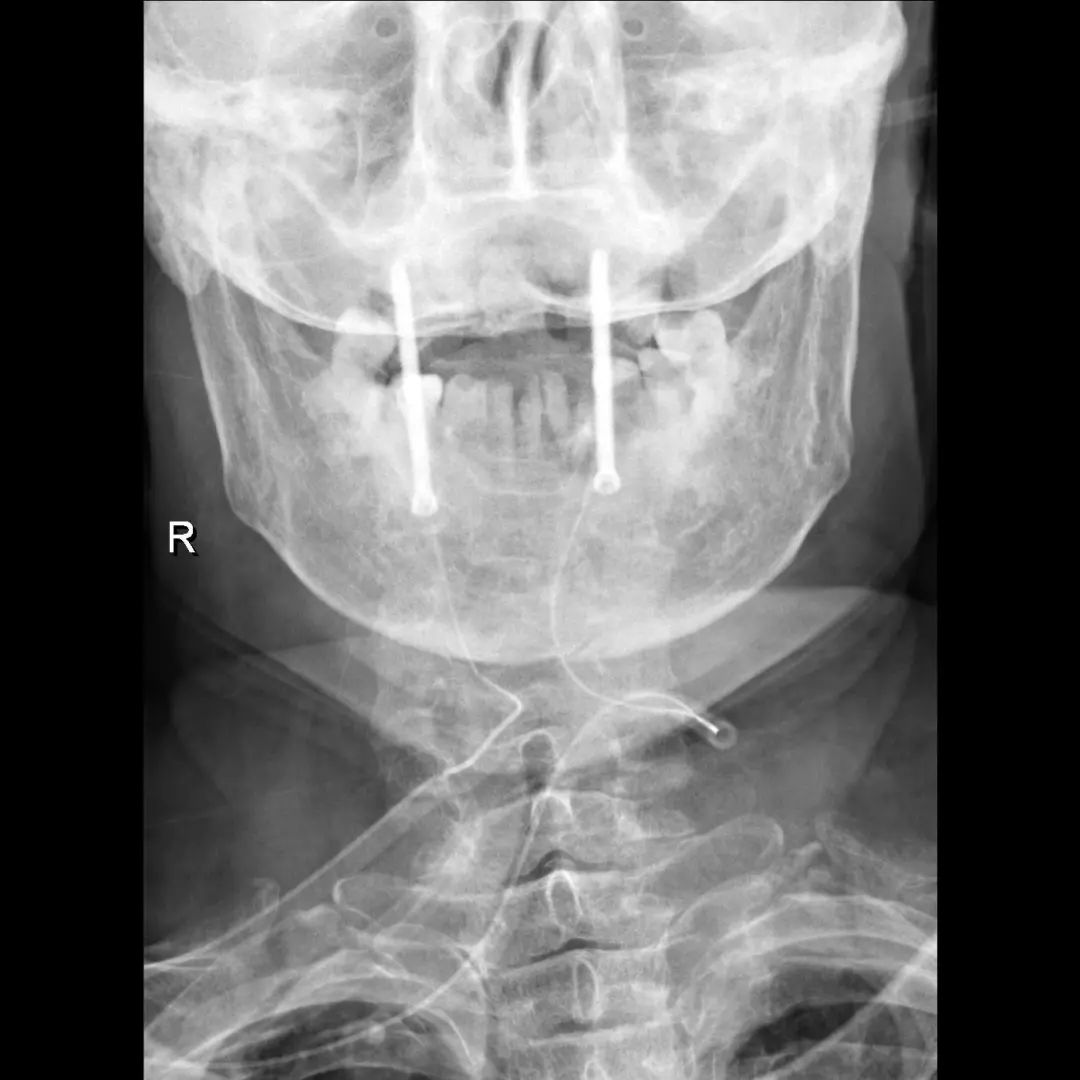

患者经充分咨询了解,选择了枣庄市立医院脊柱外科主任王存平为其治疗。面对患者和家属期盼的目光,王存平明白这是患者最后的希望,故而没有胆怯和退缩,大胆提出了齿状突骨折后路切开复位C1、2椎弓根钉棒系统固定的手术方案。由于患者年龄较大,存在脊柱严重后凸畸形,俯卧位极度困难,全麻插管难度大,麻醉风险极大。麻醉科李传东和宓云飞医师克服重重困难,成功完成麻醉。在他们得力的麻醉和监护下,王存平仔细分离、细心操作,每一步都确保动作稳稳完成,最终成功实施了手术。

经过全程监护和系统治疗,患者术后恢复良好,骨折解剖复位,复查X线及CT显示固定位置佳,术后3天下地行走,术后4天即出院回家休养。

该手术为我市首例完成C1、2椎弓根钉棒系统固定手术,填补了枣庄在上颈椎外伤手术史上的空白,展现了枣庄市立医院脊柱外科不怕困难、勇于突破、积极向上的精神面貌,也是王存平主任技术高超、胆大心细的具体体现。